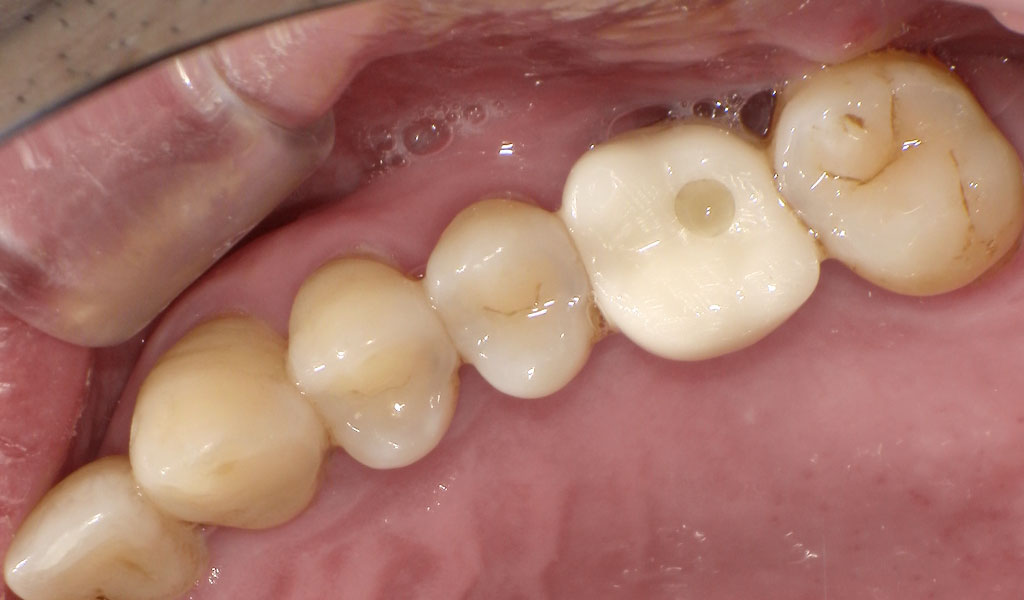

Before(左上6番)

60代男性・横浜市在住。歯周病により歯がぐらついていたため、当院にて左上6番、左下6,7番、右下5,6,7番を抜歯後、インプラント治療。人工歯はジルコニア人工歯。スクリューリテインにて固定しました。歯周病菌の数が多いため、歯周内科治療も実施しました。